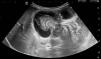

Se solicita ecografía abdominal (fig. 1), con diagnóstico de invaginación ileocecal evolucionada con posible perforación intestinal.